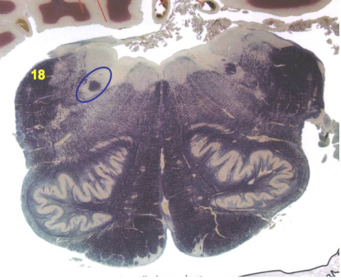

| Superior cerebellar peduncle | |

| Dentate nucleus | |

| Fastigial nucleus | |

| Anterior spinocerebellar tract | |

| Spinal nucleus of V | |

| Spinal tract of V | |

| Middle cerebellar peduncle | |

| Superior vestibular nucleus | |

| Medial lemniscus | |

| Trapezoid body | |

| Ventral trigeminothalamic tract | |

| Superior olive | |

| Longitudinal pontine fibers (corticospinal tract) | |

| Transverse pontine fibers (dark fibers) | |

| Pontine nuclei (pale) | |

| Central tegmental tract | |

| ALS | |

| Medial longitudinal fasciculus | |

| Principle nucleus of V | |

| Mesencephalic V tract | |

| Trigeminal root fibers | |

| Motor nucleus of V | |

| Cerebellar vermis | |

| Lateral lemniscus | |

| Longitudinal pontine fibers (c-spinal, c-bulbar, c-pontine fibers) | |

| Transverse pontine fibers (dark) | |